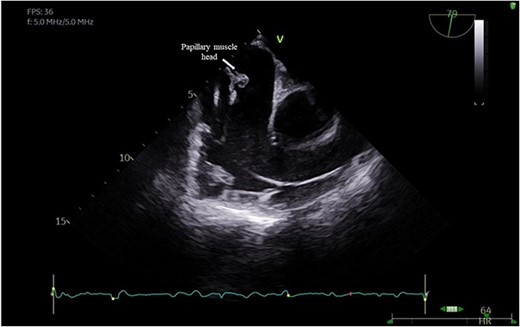

The leaflet was excised and a 27 mm Mitral Magna Ease tissue valve was implanted. He was successfully weaned off cardiopulmonary bypass and decannulated off ECMO in sinus rhythm. Post-operative ECHO showed a well seated and functioning TV prosthesis (Fig. 4).